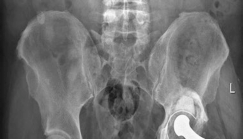

Advanced osteoarthritis bilaterally. Osteonecrosis and complete obliteration of the joint space on both sides…